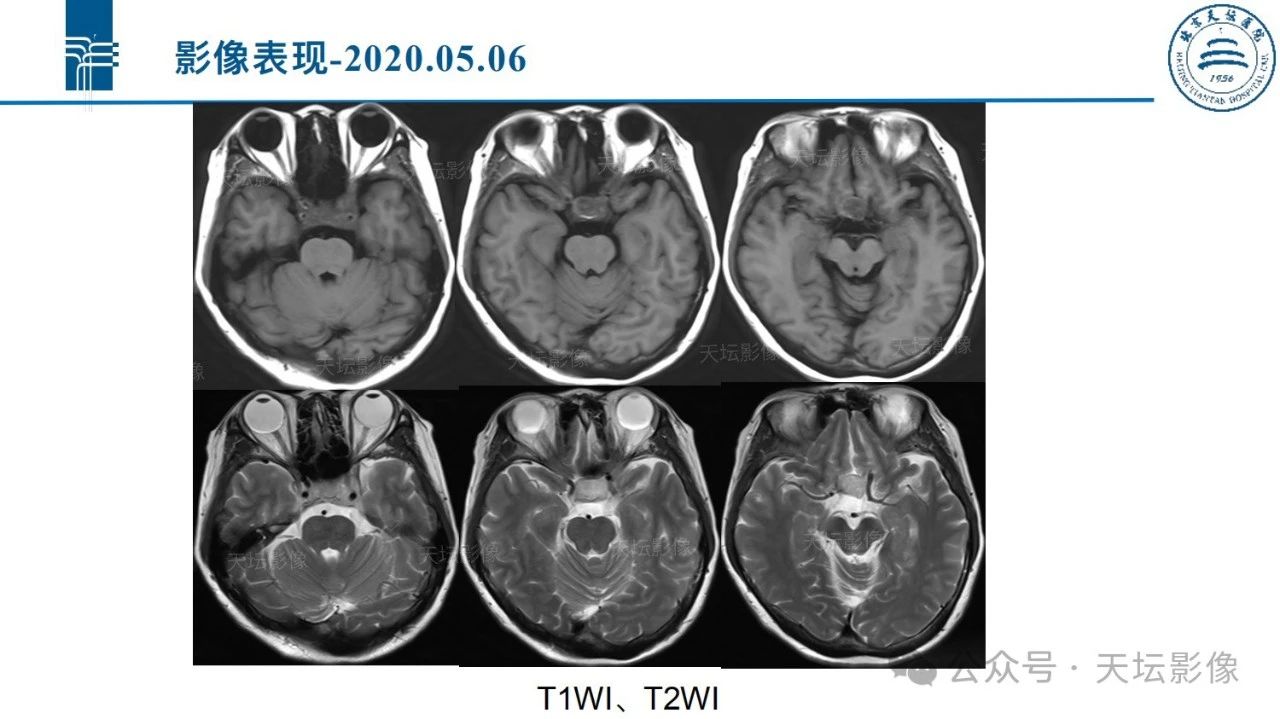

[中枢神经] 脑室外神经细胞瘤MR诊断

来源:天坛影像